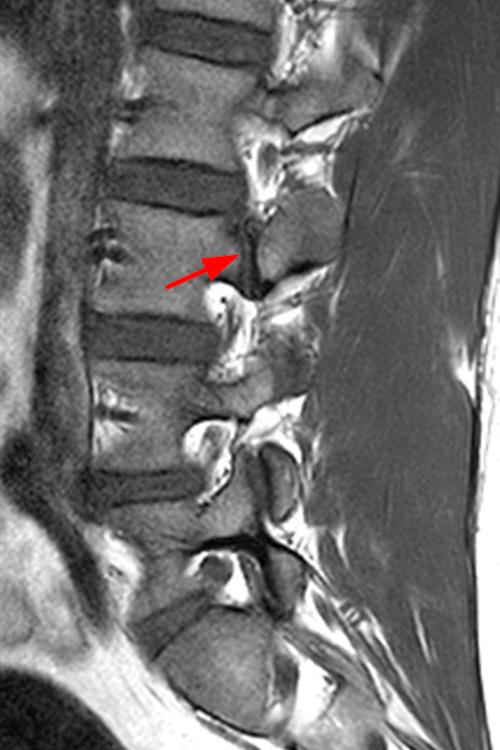

Case 1: 14-year-old female with back pain after a car accident. Axial T2-weighted (1A) and sagittal STIR (1B) images are provided. What are the findings? What is your diagnosis?

Case 1: T2-weighted axial (3A) and sagittal STIR (3B) sequences show marked cortical T2/STIR hyperintensity in the left pedicle of L5 surrounding a hypointense line (arrows) which begins at the inferior/medial margin of the pedicle and nearly completely traverses the pedicle.

Case 1: Acute left-sided pediculolysis